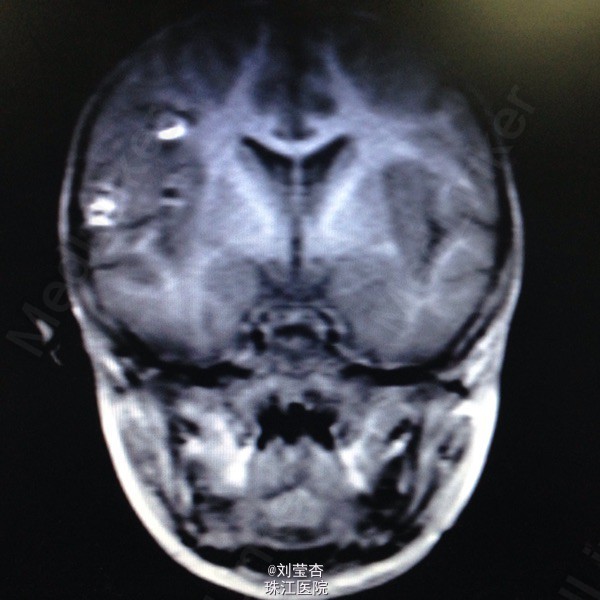

患儿女,3岁,因“咳嗽、流涕6天,发热5天,抽搐1次”入院。患儿接触家猫后出现流清涕,伴咳嗽,为间断单声咳,2天后出现发热,热峰39.5℃,予退热处理,患儿仍有反复发热,后患儿出现双眼向中上方凝视,双眼眼周肌肉抽动,伴口角流涎,无伴口周发绀、牙关紧闭,神志清楚,呼之可应,体温不详,四肢末梢温暖,四肢肌张力不高,持续约1分钟后可自行缓解。到当地医院就诊,查血常规:白细胞10.8G/L,中性粒细胞66.1%,淋巴细胞百分数27.1%,血红蛋白110g/L,血小板272 G/L,CRP4.2mg/L;胸片示支气管炎;头颅CT示右侧颞叶、双额叶多发散在脑出血。予吸氧、退热、抗感染、抗炎、补液、降颅压、止血等处理,患儿未再出现抽搐,患儿仍有反复发热,家属要求转我院进一步治疗。

查体:浅昏迷,反应一般,CRT2s,左侧耳后级颌下可触及3个肿大淋巴结,大小为0.5*0.5cm,质软,可活动,无压痛,与周围组织不粘连,双侧瞳孔等大不等圆,左侧瞳孔3mm,右侧瞳孔2.5mm,对光反射灵敏,口腔黏膜可见散在溃疡,咽部粘膜充血,双侧扁桃体Ⅰ度肿大,充血,未见黄白色脓点及分泌物,颈部稍抵抗,双肺呼吸音粗糙,可闻及大量痰鸣音,脑膜刺激症Kernig征可疑阳性,Brudzinski征可疑阳性。病毒八项:RUBE-IgG 26.8IU/Ml,CMV-IgG 117U/Ml,HSV-IgM 2.3S/CO,HSV-IgG 21.0S/CO,病毒两项:EB病毒DNA定量<5.00E+02(阳性)拷贝/mL,巨细胞病毒DNA定量9.65E+02(阳性)拷贝/mL;脑脊液常规:无色,透明,RBC 420M/L,WBC 40M/L,红细胞形态基本正常,潘氏试验(-);脑脊液单纯疱疹病毒DNA定量:单纯疱疹Ⅰ型DNA定量4.79+03(阳性)拷贝/mL,单纯疱疹Ⅱ型DNA定量低于检测下限拷贝/mL。

诊断:1.病毒性脑炎(单纯疱疹病毒感染)2.支气管肺炎。入院后予抗炎、抗病毒、抗惊厥、脱水、降颅压、促醒、输血浆,改善循环、雾化吸入、维持水电质平衡、营养支持等治疗。